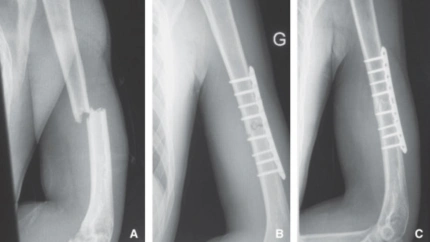

La fisura es una fractura pero sin desplazamiento del hueso

Curiosamente una fisura, también es una fractura, pero sin desplazamiento del hueso.

Hoy en "Mediodía COPE Toledo" hablamos con el Dr. Fernando Ladero sobre las causas de las fracturas, los tipos que existen y el tratamiento, que en muchas ocasiones sigue contando con el típico yeso, aunque ahora con otros materiales más higiénicos.